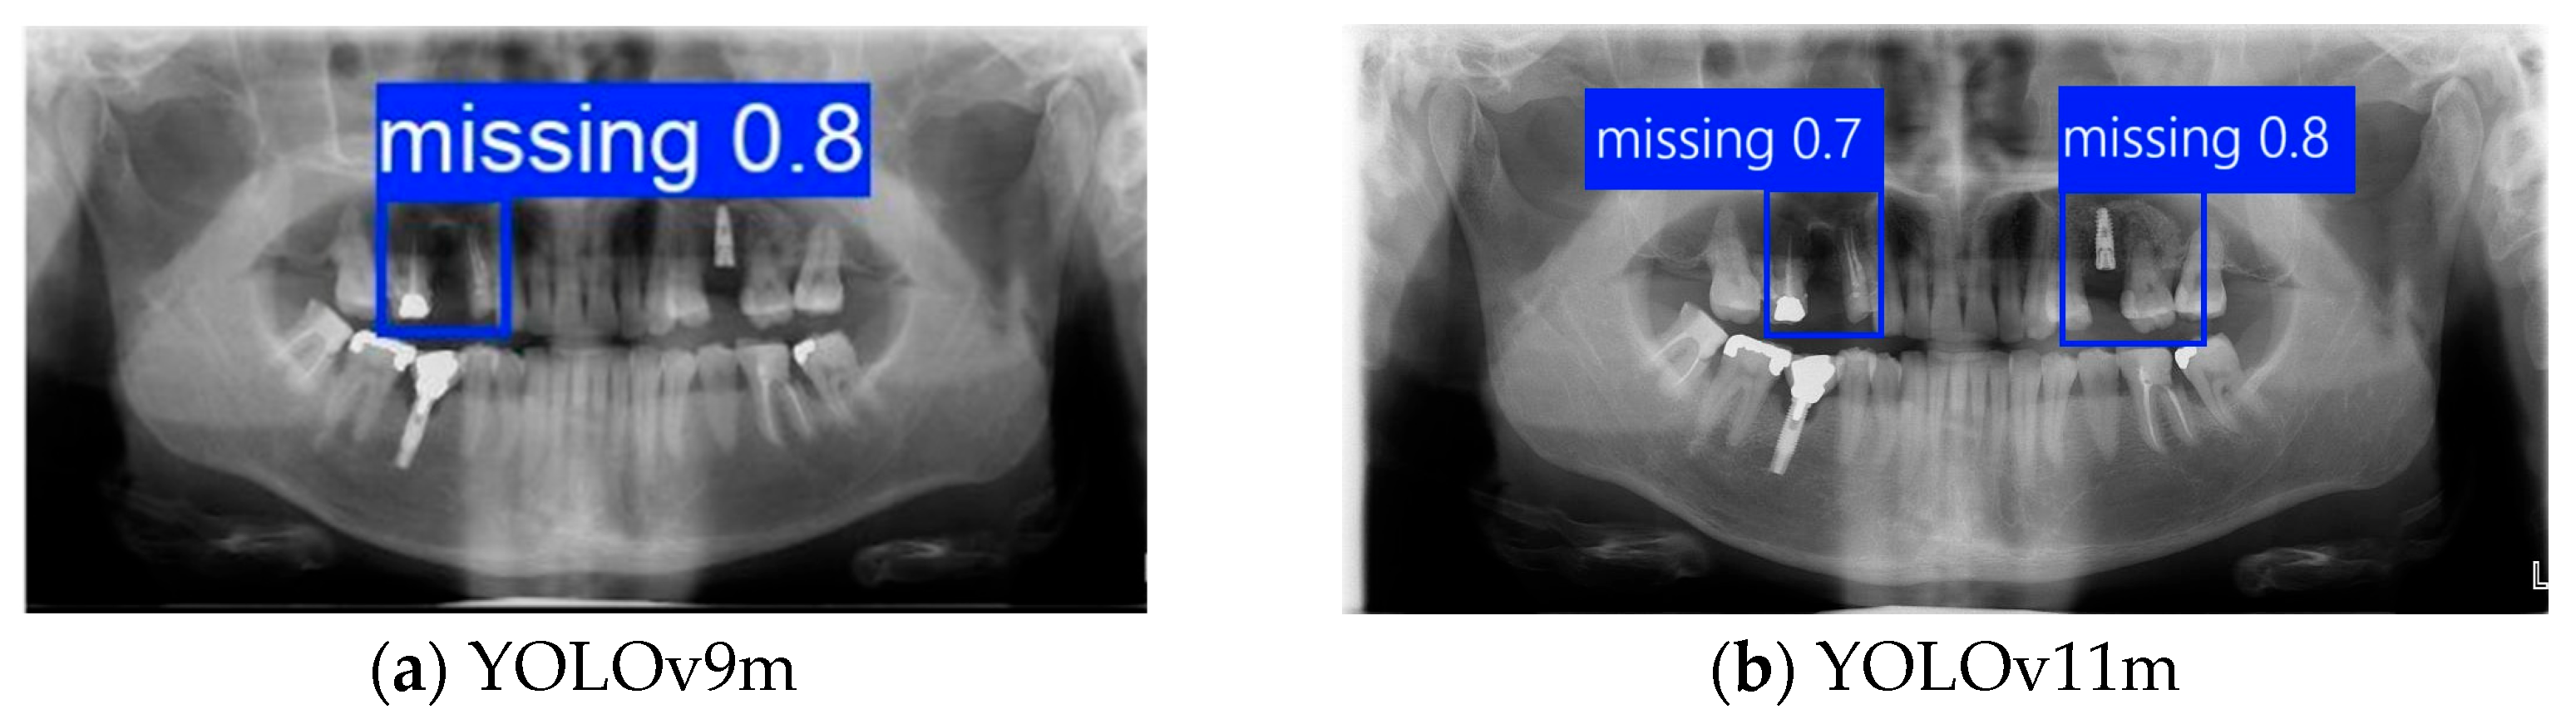

2.2. Extraction of Missing Teeth by Deep Learning Method

2.2.1. YOLO Architecture

3.1. DPR Instance Segmentation Result

| Accuracy | Precision | Recall | mAP50 | mAP50–95 | Training Time (m:s) | p-Value | McNemar’s Test | Paired t-Test | |

|---|---|---|---|---|---|---|---|---|---|

| YOLOv9m | 85.60% | 88.86% | 86.67% | 88.45% | 75.34% | 14:47 | 0.045 | - | - |

| YOLOv10m | 80.20% | 83.09% | 86.67% | 88.59% | 75.62% | 13:32 | 0.082 | 0.091 | 0.088 |

| YOLOv11m | 86.58% | 87.64% | 88.89% | 89.23% | 74.94% | 11:39 | 0.046 | 0.052 | 0.048 |

| YOLOv12m | 78.88% | 83.79% | 84.44% | 85.16% | 60.37% | 12:58 | 0.117 | 0.103 | 0.110 |

| Faster R-CNN | 75.98% | 79.63% | 80.01% | 78.23% | 59.65% | 18:15 | 0.189 | 0.2325 | 0.4295 |

| Swin-transformer | 70.98% | 71.47% | 73.86% | 67.89% | 54.62% | 22:08 | 0.207 | 0.4211 | 0.4238 |